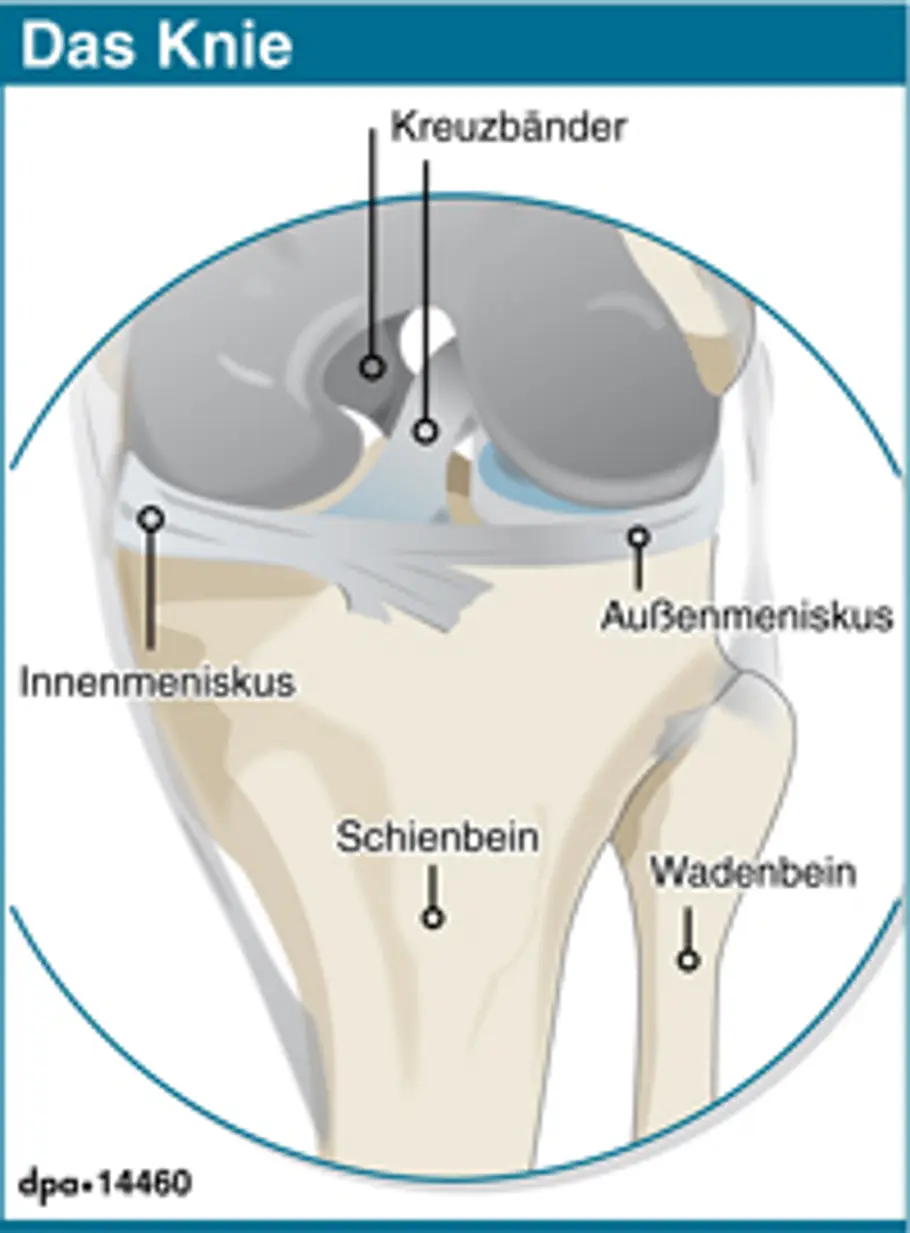

Die beiden Kreuzbänder verlaufen innerhalb des Knies tatsächlich über Kreuz. Sie verbinden die Oberschenkel- mit den Unterschenkelknochen und sorgen so (gemeinsam mit den Seitenbändern) dafür, dass das Knie stabil ist. Dabei trägt das vordere (hier hellere) Kreuzband eine größere Last, als das hintere. Theoretisch kann ein Mensch zwar auch ohne Kreuzbänder laufen und sogar Sport machen. Allerdings werden dadurch die anderen Strukturen im Knie – vor allem Außen- und Innenmeniskus, sowie die Knorpel – so stark belastet, dass sie Schaden nehmen. Es gibt aber sogar Fußballer, die nach einem Kreuzbandriss ohne die stützenden Bänder weiterspielen. So zum Beispiel der Reserve-Keeper von Hannover 96, Markus Miller. In den meisten Fällen werden bei einem Kreuzbandriss auch noch weitere Kniestrukturen, wie Innen- oder Außenband oder Innen- oder Außenmeniskus beschädigt. Eine typische Kombination besteht aus vorderem Kreuzband, Innenmeniskus und Innenband – die sogenannte "Unhappy Triad" (unglücklicher Dreiklang).